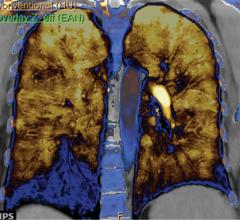

Patient presented to UH Case Medical Center’s emergency department with severe chest pain, suggesting either a pulmonary embolus or aortic dissection.